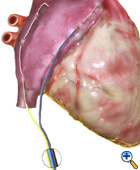

Figure 2. |

Right Atrial Cardioversion Wire Placement

The right atrial cardioversion wire (yellow) is placed at the end of the operation right before or just after the patient is weaned the CPB machine. In the beating heart patient, right after the bypass grafts have been performed, the wire is placed. The wire is placed within 5mm of the SA node linear fashion with 2-4 bites of the atrial epicardium. The needle from the wire is cut and small crimp is made in the distal end of the wire. The wire is then draped laterally along Waterston's Groove down to the inferior vena cava. This will allow 3 to 5 cm of wire to contact the epicardium. The wire is then brought out through the right side of the chest and secured to the skin with suture. A cardioversion connector is attached to the wire.

Right Atrial Pacing Wire Placement

The right atrial pacing wire (black/blue) is placed after the right cardioversion wire. The wire is placed on the atrial appendage. The wire is placed in a linear fashion with 2-4 bites of the atrial epicardium. The needle from the wire is cut and small crimp is made in the distal end of the wire. The wire is then brought out through the right side of the chest and secured to the skin with suture.